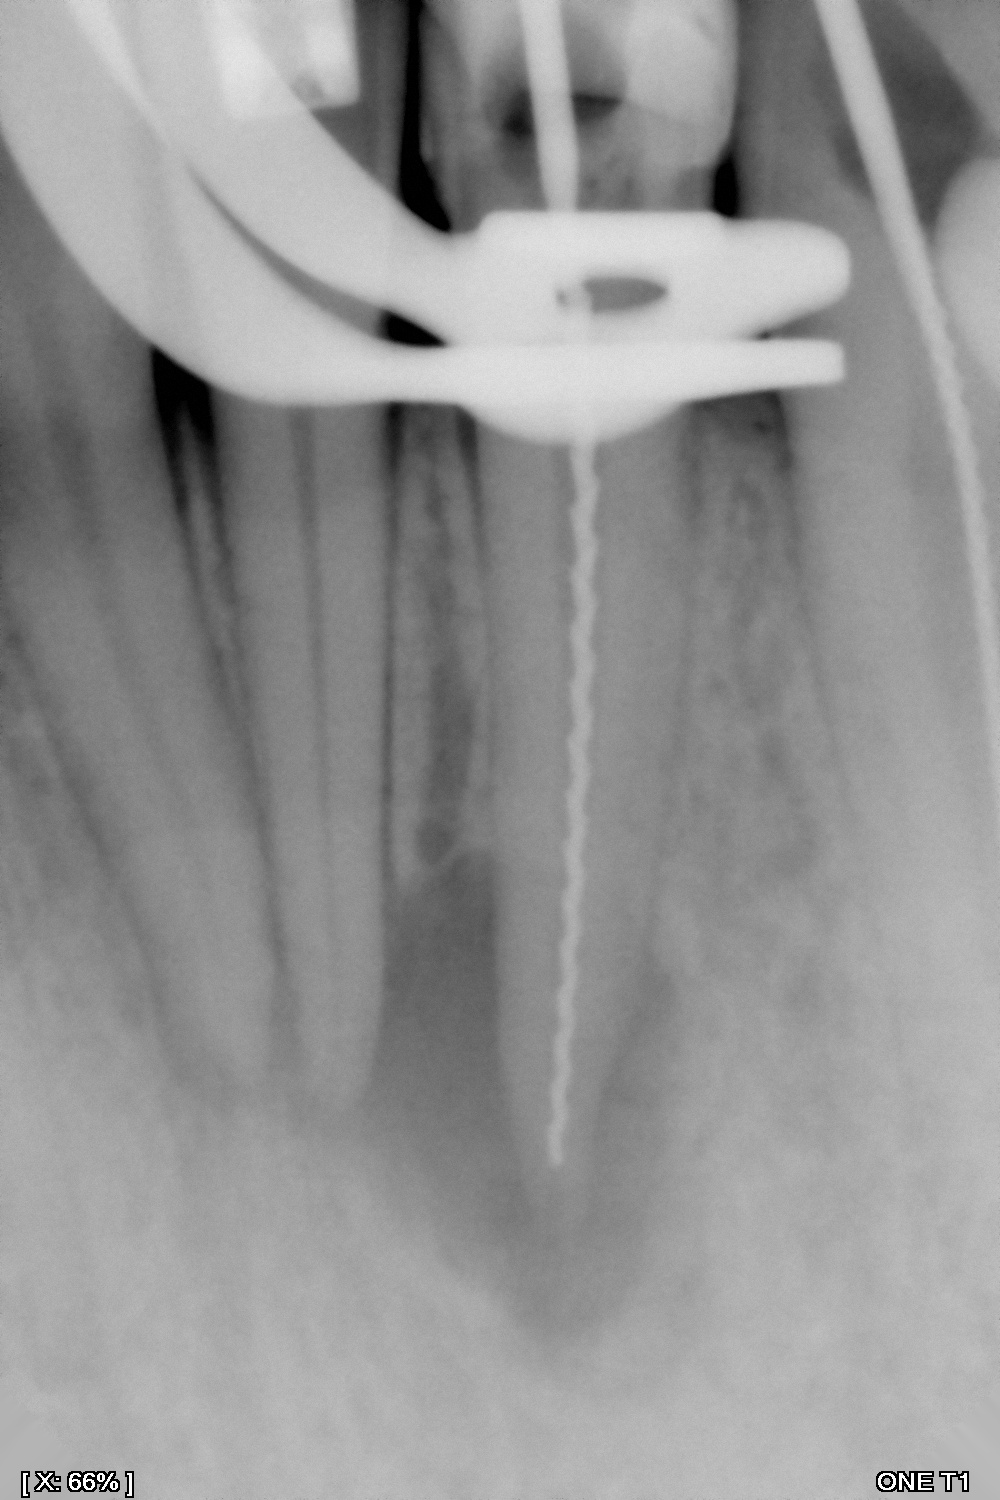

Es la especialidad que se encarga de retirar el nervio del diente cuando éste ha sido afectado por una caries, por un golpe o simplemente por requerimiento de un procedimiento de rehabilitación que esté causando sintomatología.

Y en DentPro realizamos tratamientos endodónticos con la más avanzada tecnología, utilizando sistemas rotatorios y radiografías digitales.